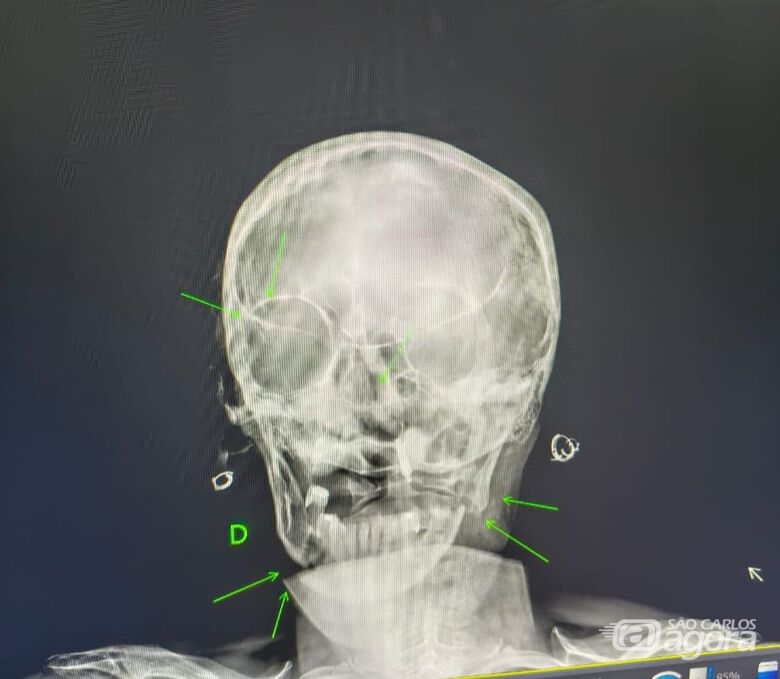

Imagem de raio-x mostra fraturas sofridas pela mulher - Crédito: SCAUm homem de 29 anos foi preso em flagrante após agredir a própria mãe, de 55 anos, e o irmão, de 20 anos, durante uma briga familiar ocorrida no início da tarde deste domingo (29), no bairro Jardim Mariana, em Ibaté.

A vítima foi encaminhada ao hospital municipal de Ibaté, onde os médicos constataram fraturas no maxilar, clavícula e região occipital, além de suspeita de traumatismo cranioencefálico. Devido à gravidade do quadro, ela foi transferida para a Santa Casa de São Carlos, onde permanece internada.